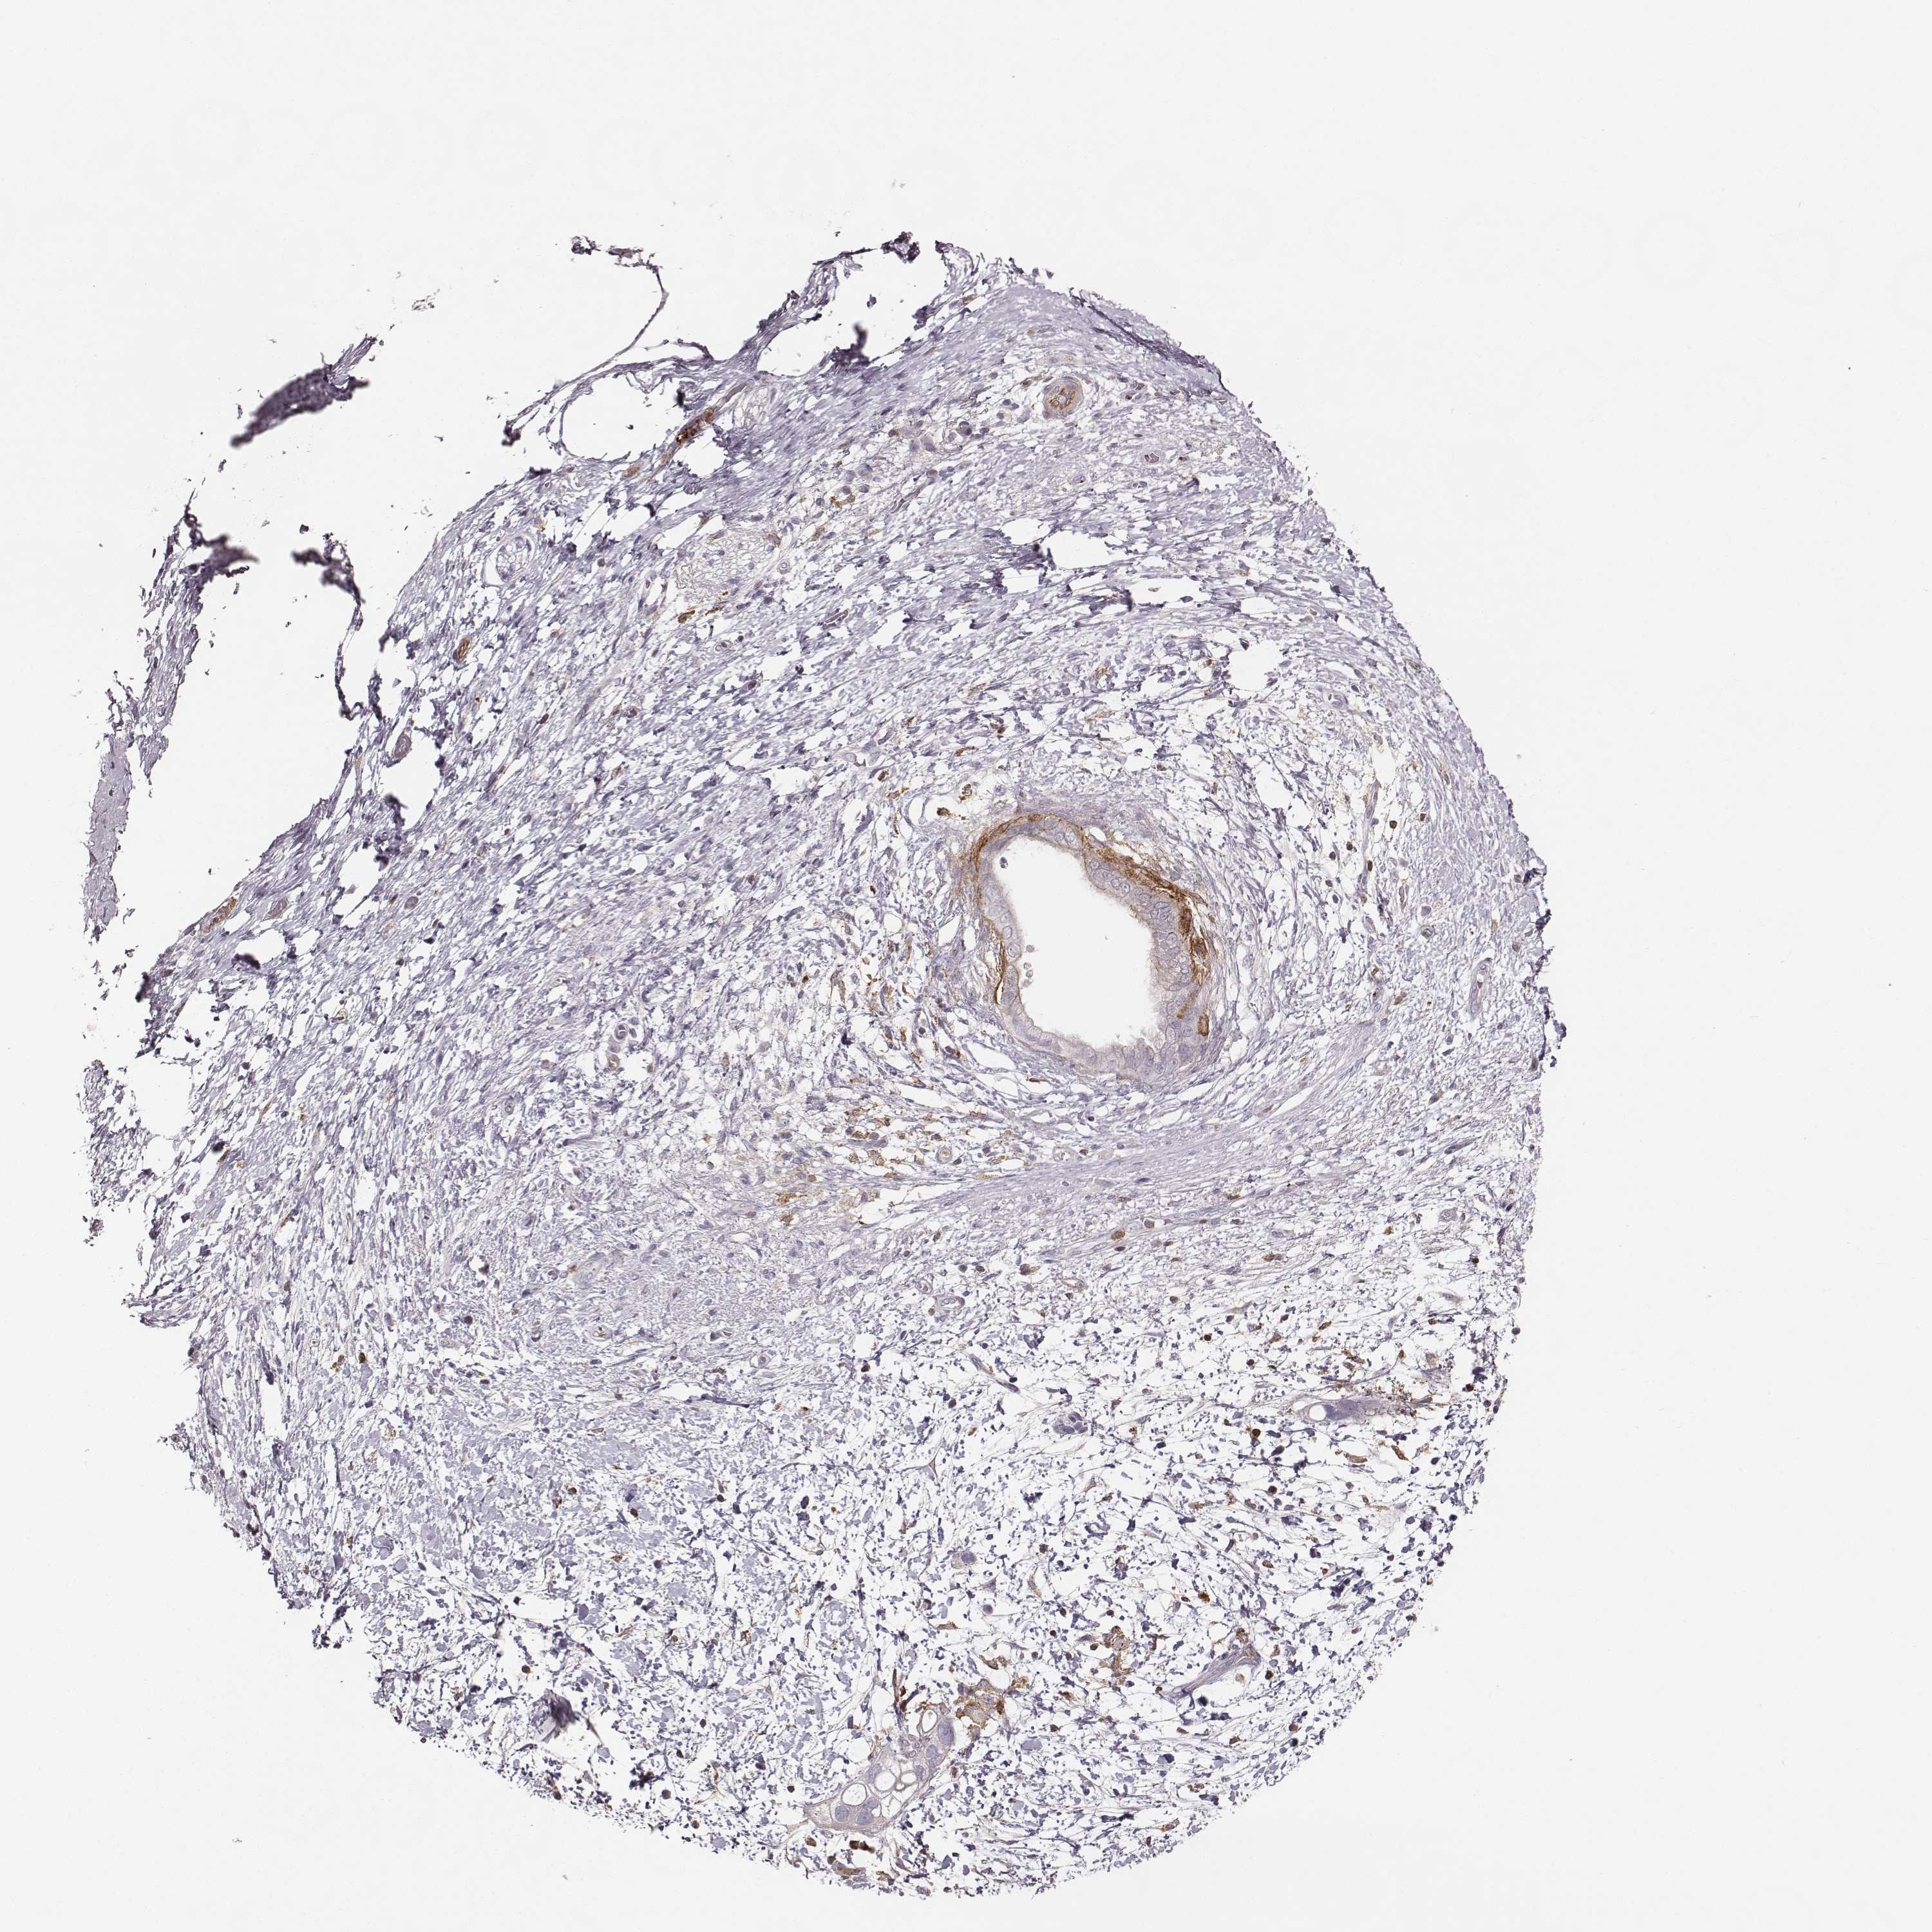

PANCREATIC CANCER - Protein expressioni

A mouse-over function shows sample information and annotation data. Click on an image to view it in a full screen mode. Samples can be filtered based on level of antibody staining by selecting one or several of the following categories: high, medium, low and not detected. The assay and annotation is described here.

Note that samples used for immunohistochemistry by the Human Protein Atlas do not correspond to samples in the TCGA dataset.

Antibody stainingi

Antibody staining in the annotated cell types in the current human tissue is reported as not detected, low, medium, or high, based on conventional immunohistochemistry profiling in selected tissues. This score is based on the combination of the staining intensity and fraction of stained cells.

Each image is clickable and will lead to virtual microscopy that enables deeper exploration of all samples and also displays staining intensity scores, fraction scores and subcellular localization as well as patient and tissue information for each sample.

Antibody HPA004835

Antibody HPA073497

Antibody CAB009321

Antibody CAB075747

Adenocarcinoma, NOS